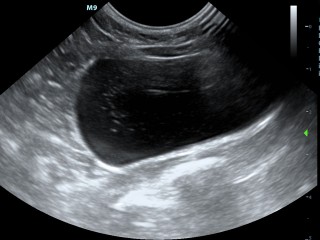

Het is mogelijk om vanaf dag 21 na dekking te kijken of uw teef of poes drachtig is. Het is ons advies om te wachten met de drachtecho tot minimaal 25 dagen dracht. Dan zijn de kloppende hartjes goed zichtbaar, en is het goed te zien of er normale groei en ontwikkeling van de vruchtjes is.

Hieronder zie je een aantal foto's van de buik met achtereenvolgens; blaasontsteking, blaastumor, vroege dracht hond 19 dagen, vergrote eierstok, lever, nier.